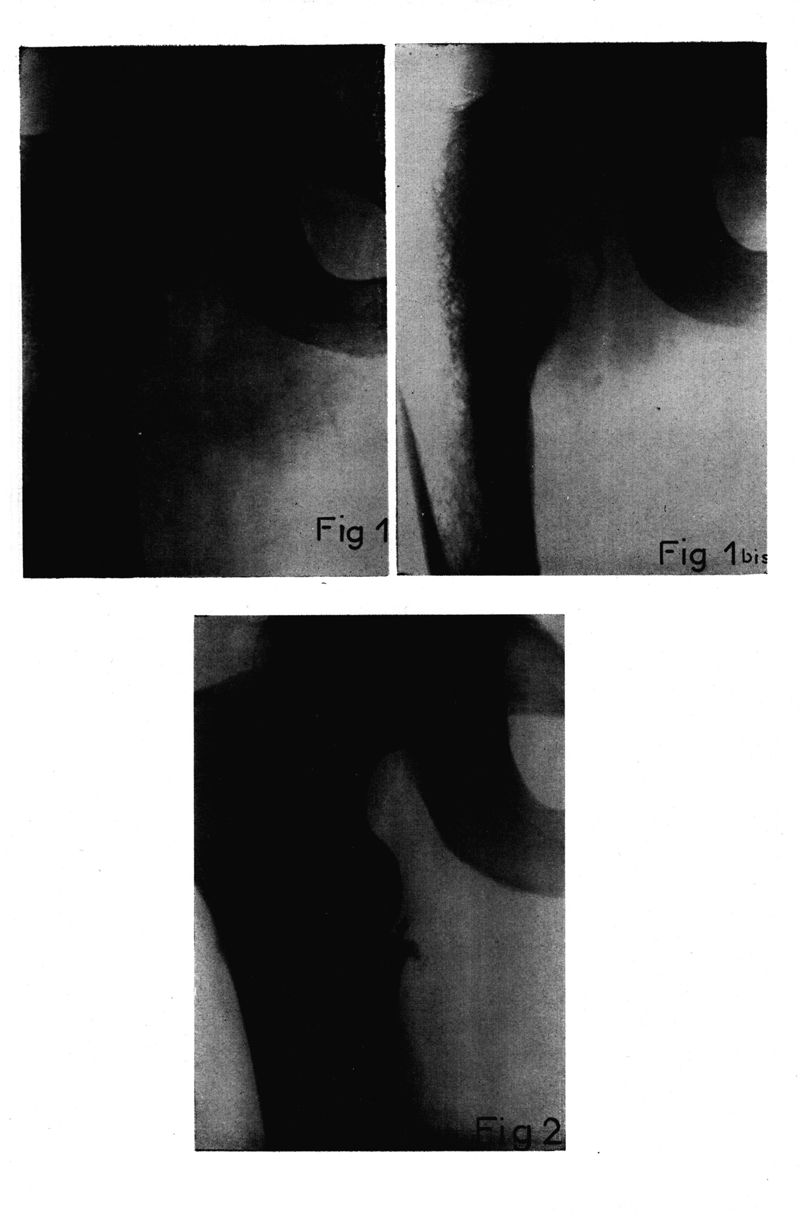

Médecine tropicale : Revue du corps de santé colonial

. - Marseille : Ecole d'application du service de santé des troupes coloniales, 1956.